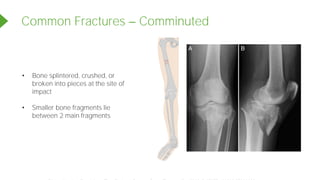

Common Fractures Comminuted

• Bone splintered, crushed, or

broken into pieces at the site of

impact

• Smaller bone fragments lie

between 2 main fragments